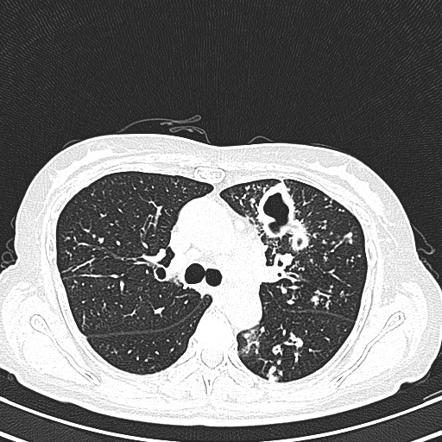

结果发现,奶奶的双肺都有结核病灶,且有空洞形成,病情比小孩严重多了。

- 空洞型肺结核,也就是肺结核的病灶,看上去就像肺上“烂”了个“洞”。由于病灶中有被结核杆菌破坏的组织,坏死物质沿着支气管、气管排出体外后,就留下了空洞,坏死组织里面结核分枝杆菌的浓度是很高的。

- 胸部X线或者CT发现肺结核可能,即使没有症状也应该高度怀疑。